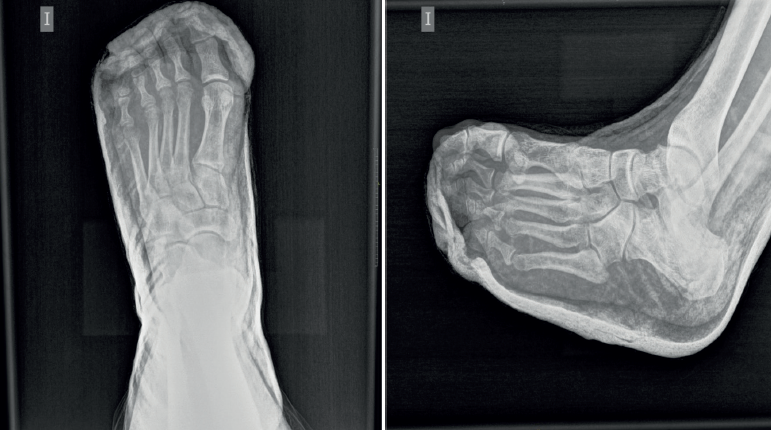

Figura 1. Radiografías dorsoplantar y oblicua del pie izquierdo en las que se aprecia la incongruencia anatómica de la tercera a la quinta articulaciones metatarsofalángicas.

En el estudio radiográfico del pie se observó una luxación dorsolateral de la tercera a la quinta articulaciones metatarsofalángicas sin fracturas asociadas (Figura 1).